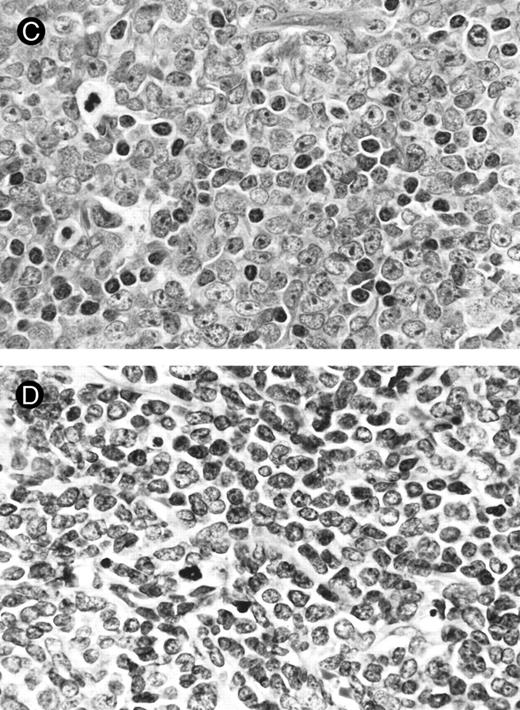

Morphology.The bone marrow and peripheral blood smears of all patients (nos. 1 and 5 at relapse) showed L2-shaped leukemic cells of various sizes, with moderately irregular nuclei, prominent nucleoli, and pale cytoplasm (Fig 1). Cytoplasmic granules or Auer's rods were not recognized in bone marrow smears and in touch imprints of biopsied specimens. Less than 3% of leukemic cells showed cytochemical MPO reactivity in all cases. The leukemic cells were histochemically negative for α-naphthol AS-D chloroacetate esterase, α-NB esterase, and PAS. Lymph node biopsies was obtained from six patients (nos. 1 through 4, 6, and 7) and needle biopsy specimen of a mediastinal tumor was available for patient no. 5. All these biopsied specimens morphologically showed diffuse infiltration by monotonous proliferation of immature mononuclear cells (Fig 2). In most of the affected lymph nodes, such infiltrates showed a T-zone distribution with sparing of follicles. The component cells had a similar blastic morphology to those seen in bone marrow or peripheral blood. These findings seriously pose the differential diagnostic problem from lymphoblastic lymphoma (LBL); indeed, a diagnosis of LBL was tentatively made for four of the patients (nos. 1, 2, 5, and 6).

Lymph node biopsies of patients no. 1 (A and B), no. 3 (C), and no. 4 (D). (A) Diffuse infiltration of tumor cells is noted in a T-zone area with sparing of follicles (original magnification × 100). (B and C) The component cells show blastic morphology with round to moderately irregular nuclei, small to intermediate-sized nucleoli, and scant cytoplasm (original magnification × 600). (D) The tumor cells show irregular nuclei with inconspicuous nucleoli.